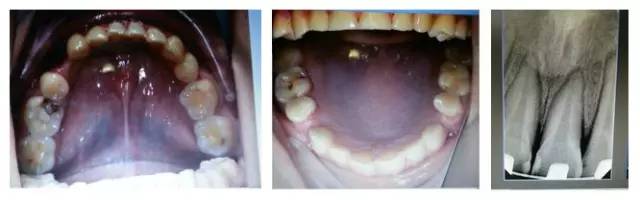

您是否首先會(huì)想到,患者的牙齒是受外力撞擊引起的牙周膜急性創(chuàng)傷?或是(牙合)創(chuàng)傷引起?如果是創(chuàng)傷,這種創(chuàng)傷是如何形成的呢?權(quán)老師提示一,患者并無外傷史,進(jìn)食很小心;提示二,從口內(nèi)照片可得知患者前牙無接觸,(牙合)創(chuàng)傷從何而來呢?

群里多位同仁已經(jīng)發(fā)現(xiàn)了它的不和諧之處,劉坦,劉曉強(qiáng)等多位醫(yī)生先后發(fā)現(xiàn):患者前伸(牙合)后牙有干擾。其他同仁也同時(shí)提出或需要進(jìn)行適當(dāng)?shù)恼{(diào)(牙合),或使用后牙(牙合)墊抬高后牙咬合,方能解決急性創(chuàng)傷。仔細(xì)看口內(nèi)的照片,從咬合的觀點(diǎn)和理論角度出發(fā),您捕捉到什么信息了嗎?

由上圖可知,患者全口牙齒磨耗較重,尖牙牙尖磨耗,無法起到引導(dǎo)和保護(hù)作用,上前牙牙根短,上中切牙腭側(cè)面邊緣嵴消失,

由此推斷:尖牙牙尖磨耗,患者在前伸(牙合)運(yùn)動(dòng)時(shí),引導(dǎo)不足,前牙的接觸面過大,受力較大;患者在側(cè)方(牙合)運(yùn)動(dòng)時(shí)下前牙沒有了引導(dǎo),會(huì)直接對(duì)側(cè)切牙造成撞擊;再加上前牙根較短,無法耐受,引起(牙合)創(chuàng)傷,繼發(fā)牙髓癥狀;失去尖牙保護(hù)(牙合),加重了牙齒的磨耗。